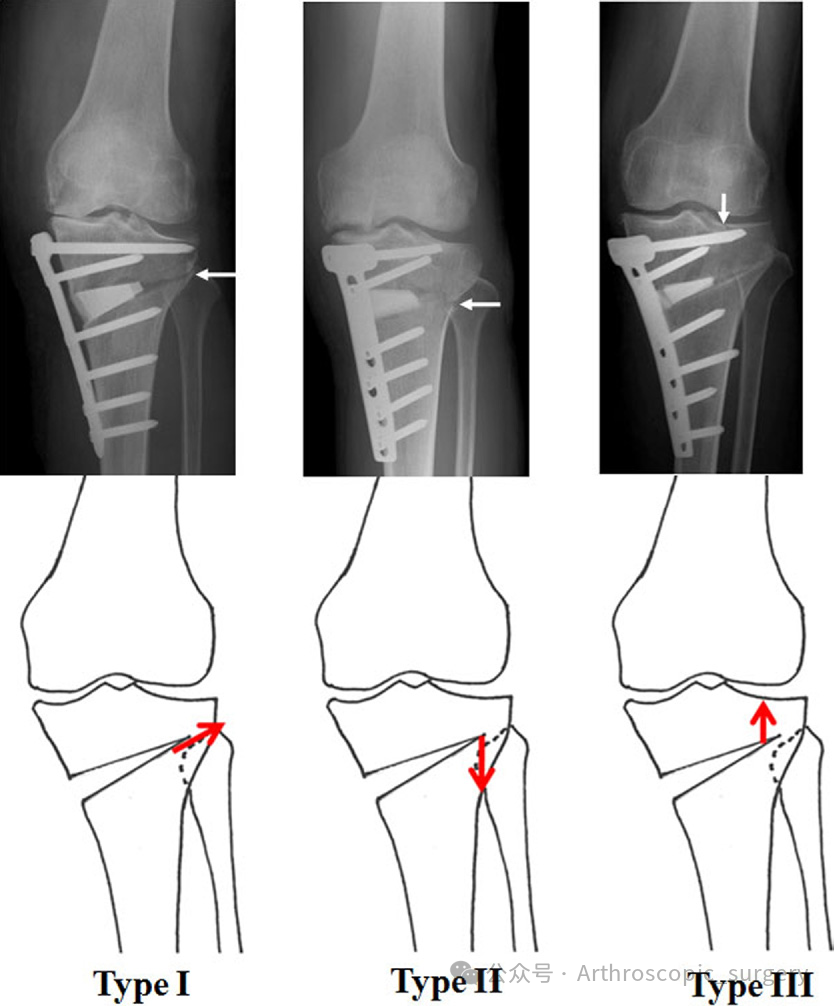

共识对颌骨折进行了分类,并基于Takeuchi等分类法,将其分为I型、Ⅱ型和Ⅲ型。

对于 I型骨折,可以采用常规内固定处理;对于 Ⅱ型和Ⅲ型 骨折,则建议使用额外的螺钉或小型锁定钢板固定(推荐强度:中等)。

这为外科医生提供了明确的处理依据,有助于减少术后不稳定性。